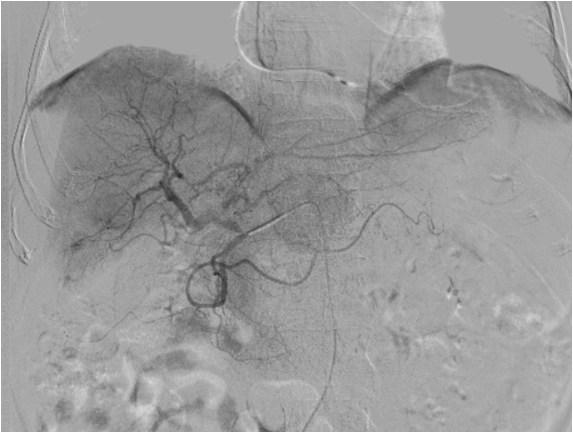

Transarterial Chemoembolisation (TACE) is a minimally invasive, image-guided treatment used primarily for liver cancer, especially hepatocellular carcinoma (HCC). It is commonly recommended when surgery or ablation is not suitable.

Liver tumors receive most of their blood supply from the hepatic artery, whereas healthy liver tissue is supplied mainly by the portal vein. TACE uses this difference to selectively target the tumor.

During the procedure, chemotherapy is delivered directly into the tumor-feeding arteries, followed by embolic agents that reduce blood flow. This traps the chemotherapy within the tumor and deprives it of oxygen and nutrients, limiting tumor growth while reducing systemic side effects.

Transarterial Chemoembolization (TACE) is a minimally invasive, image-guided procedure used to treat liver tumors. Through a tiny catheter placed in an artery, targeted chemotherapy is delivered directly to the tumor, followed by embolization to block its blood supply—maximizing tumor control while minimizing effects on the rest of the body.